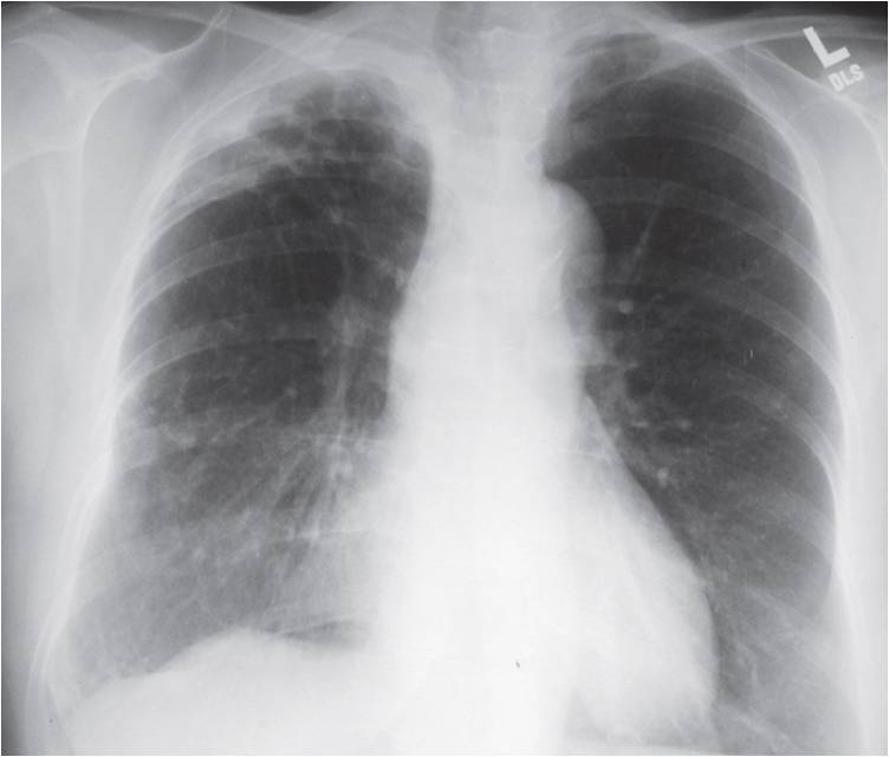

그는 이후 몇 개월간 결핵약을 '배부르게' 먹고, 검진을 받을 때마다 흉부 엑스레이 촬영에서 폐결핵 흔적(Old Pulmonary Tb)이라는 누구도 알아주지 않는 훈장을 달았다고 한다.